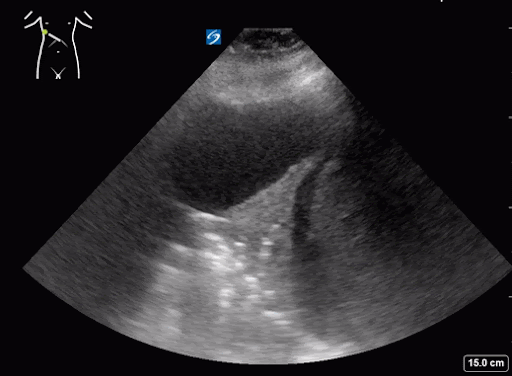

What do we see in this pt’s US?!

Right lung base

Patient’s CT chest came back positive for right sided aspiration pneumonia and right lung collapse secondary to pleural effusions.